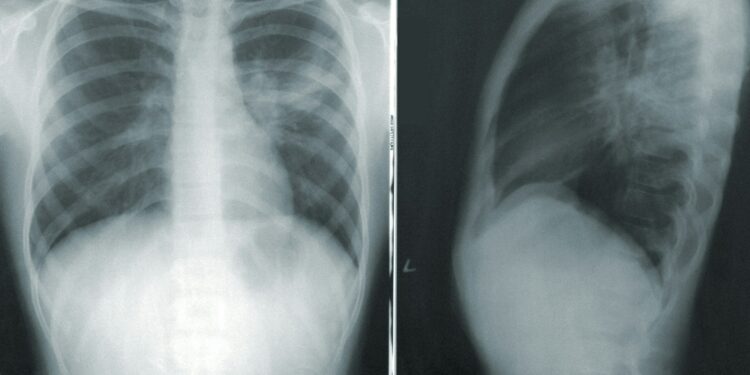

While clinical trials have validated the benefits of screening using computed tomography (CT) scans, real-world evidence has been limited. This study, focusing on U.S. veterans, sought to evaluate the impact of screening on lung cancer diagnoses.